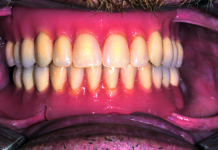

La protesi fissa tipo “Toronto Bridge”

Tempi rapidi, cicli di lavorazione ridotti ma è proprio così?

La protesi fissa “TORONTO BRIDGE“ è una protesi fissa totale completa con flangia rosa (...